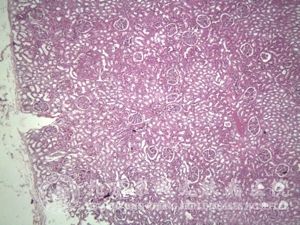

北京京城皮肤医院指出:肠病性肢端皮炎的组织病理表现为皮肤活检无特异性,呈现亚急性皮炎组织病理改变。 上部及血管周围淋巴*和组织炎性浸润,伴表皮*间海绵状水肿、表皮内水疱,肠道嗜酸性粒*的超微结构有损害。